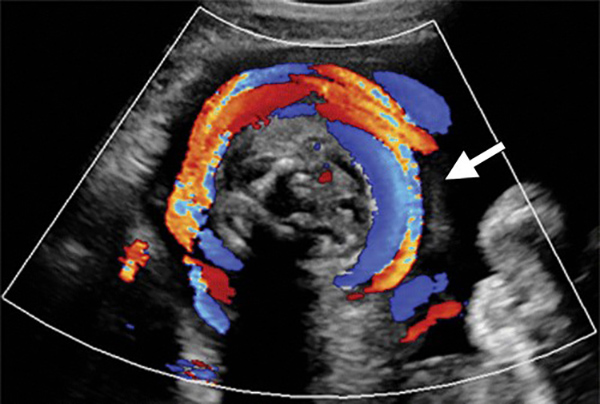

Nếu chỉ quan sát bằng mắt thường hoặc dựa vào các dấu hiệu thì không thể chẩn đoán được là dây rốn có quấn cổ hay không. Siêu âm sản khoa có thể chẩn đoán sự hiện diện của dây rốn và suy ra số vòng dây rốn quấn cổ. Tuy nhiên, điều này phụ thuộc vào chất lượng hình ảnh siêu âm và kinh nghiệm của bác sĩ. Các bác sĩ xem xét nhiều góc độ của cổ thai nhi để xác định dây rốn.

Nếu dây rốn quấn quanh 3/4 cổ thai nhi thì được xác định chắc chắn là dây rốn. Nếu dây chỉ được bao quanh một nửa cổ thì không cần lo ngại.

Qua hình ảnh siêu âm đen trắng, khả năng phát hiện ra dây rốn quấn cổ là 70%, với siêu âm Doppler màu, độ chính xác từ 83 – 97%. Siêu âm là cách giúp xác định dây rốn có quấn cổ hay không, quấn mấy vòng, nhưng không thể can thiệp để tháo dây rốn.